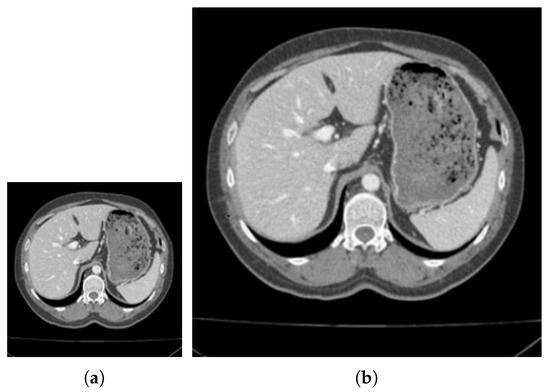

CT image segmentation of liver. (a) Original image. (b) True image. (c) SLIC. (d) SNIC. (e) Proposed.

4.2. Verification of Medical CT Images with Proposed Method

Figure 9 and Figure 10 are the segmentation results on the CT image of the vertebrae and the CT image of the liver, respectively. Although this article uses downscaling in the process of improving the algorithm to reduce the number of pixels, which caused a certain degree of edge information loss. It can be seen that the segmentation effect of the improved SNIC algorithm is similar to the original algorithm. Compared with SLIC and SNIC, the algorithm in this paper is more sensitive to texture features and can segment edges accurately, which is more practical.

Table 1 and Table 2 show the comparison of evaluation coefficients on vertebral CT data and liver CT data respectively. It can be seen that the improvement of the SNIC algorithm in this paper can ensure that the segmentation accuracy of medical CT in the segmentation of medical images does not decline, and the segmentation speed has been significantly improved. Compared with SLIC and SNIC, the segmentation time is saved by 60% to 70%.

In Table 1 and Table 2, we can see that when segmenting vertebral images, compared with SNIC, the proposed method of Dice, Jaccard, and CCR are all higher by 0.3%, but the time is reduced by 6.2 s; in segmentation In the liver image, the Dice, Jaccard, and CCR of the proposed method are 0.2%, 0.7%, 0.8% higher, respectively, and the time is shortened by 8.3 s, which is one third of the time used by the SNIC method.